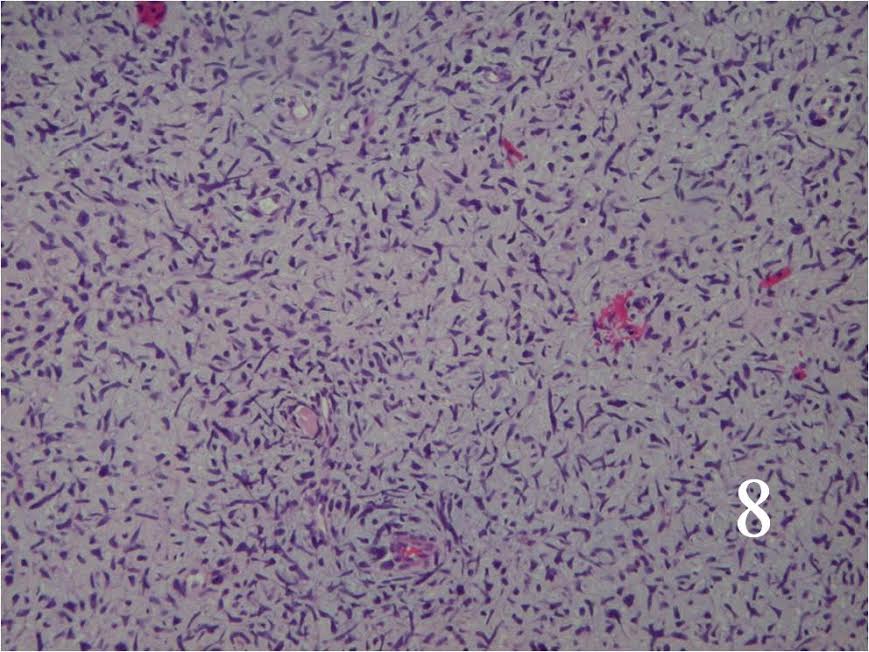

Microscopic

- Resembles fibrosarcomas

- Usually high grade features

- Spindle cells with markedly irregular contours (Fig. 7, 8)

- Nuclei are comma-shaped

- Cells are arranged in sweeping fascicles

- Extensive perineural and intraneural spread

- Proliferation of tumor into subendothelial zone of the vessels

Fig. 7 Low power and high power (Fig. 8) magnification on H&E staining shows a spindle cell neoplasm with high cellularity, abnormal mitotic features and nuclear atypia. The cells are arranged in a somewhat fascicular manner.